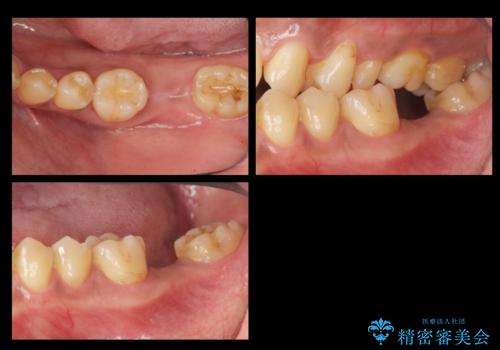

- 30代男性

- 治療期間

- 6ヶ月

- 治療回数

- 5-10回

- 奥歯が割れたあと、他院で抜歯したところにインプラントを希望して来院。2回法で行いました。